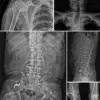

In 2022, a 73-year-old Korean man was hospitalized for a stroke. During his evaluation, he described a 30-year history of widespread joint pain he had self-treated with gold thread acupuncture. X-rays revealed thousands of the embedded threads throughout his body

In 2022, a 73-year-old Korean man was hospitalized for a stroke.

During his evaluation, he described a 30-year history of widespread joint pain he had self-treated with gold thread acupuncture.

X-rays revealed thousands of the embedded threads throughout his body. ‘This man had been using gold thread acupuncture for decades without any medical supervision,’ said a neurologist involved in his care. ‘His symptoms were so severe that he had to be hospitalized, and it was only through imaging that we realized the true extent of the problem.’